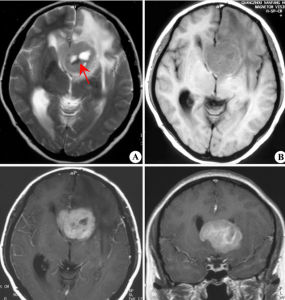

(多形性膠質母細胞瘤):同樣需要手術來達到組織病理診斷和減小腫瘤體積。術後放療(劑量在60Gy左右)。化療手段包括卡莫司汀,聯合方案PCV(甲基苄肼,環己亞硝脲和長春新鹼),或者替莫唑胺用來對腫瘤生長進行控制。分類

膠質瘤的診斷,根據其生物學特徵、年齡、性別、好發部位及臨床過程進行分析,在病史及體徵基礎上,採用電生理、超音波、放射性核素、放射學及核磁共振等輔助檢查,定位正確率幾乎是100%,定性診斷正確率可在90%以上。腦膠質瘤由於腫瘤呈浸潤性生長,與腦組織無明確分界,難以徹底切除,手術治療的原則是在保存神經功能的前提下儘可能切除腫瘤。早期腫瘤較小又位於適當部位者可爭取全部切除。位於額葉的腫瘤,可作腦葉切除。當額葉或顳葉腫瘤範圍較廣不能全部切除時,可同時切除額極或顳極作內減壓術。腫瘤位於運動、言語區而無明顯偏癱、失語者,宜注意保存神經功能,適當切除腫瘤,避免發生嚴重後遺症。腦室腫瘤宜從非功能區切開腦組織進入腦室,儘可能切除腫瘤,解除腦梗阻。位於丘腦、腦幹的膠質瘤,除小的結節性或囊性者可作切除外,一般作分流術,緩解增高的顱內壓後,進行中醫藥綜合治療。

膠質細胞瘤的生長特點為浸潤性生長,與正常腦組織無明顯界限,多數不限於一個腦葉,向腦組織外呈指狀深入破壞腦組織,偏良性者生長緩慢,病程較長,惡性者瘤體生長快,病程短。目前國內外對於膠質瘤的治療普遍為手術、中醫藥、放療、化療、X刀、和γ刀。